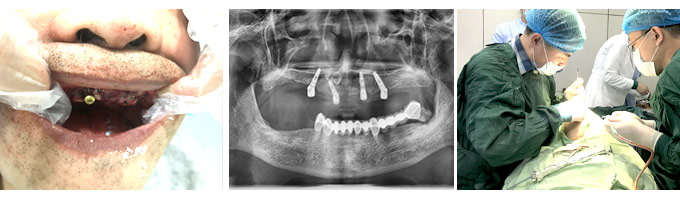

种植牙并不是真的种上自然牙齿,而是将纯钛金属制成的牙根,植入缺牙区的牙槽骨内,这种牙根与人体兼容性高,没有副作用,等到牙根与牙槽骨产生骨结合,再在牙根上安装牙冠。种植牙已被口腔医学界认可为缺牙的优选修复方式,植得种植牙由于牙根深植牙骨内,坚固耐用,功能和美观上几乎和真牙一样。

大连康贝佳口腔的院长介绍,种植牙从开始准备到成功植入,患者只需进行一次微创治疗,一天的时间就可以完成半/全口牙缺失的修复,且种植过程无不适感,不会影响日常生活和工作。可达到无创伤、时间迅速、咀嚼功能强、稳定性好、无磨损真牙、美观自然、易保持口腔清洁卫生等特点。同时,种植后牙齿可以像真牙一样正常咀嚼,也能达到和真牙一样的咀嚼力度,不管是硬的、粘的食物都毫无问题。>>>种植牙可以使用多久

种植修复是一项对医生技术十分考究的手术,它要求医生必须要有快速的速度、熟练的技术以及丰富的种植经验。种牙就像盖房子,我必须把地基打牢固,才能让我的患者“住”得安心,住得长久。

为了让顾客都能种好牙、放心种牙,康贝佳还邀请了享誉国际种植领域,在业界成功实施了两万例疑难种植手术的意大利医生法布里奇奥博士、北京博士后吴高谊助阵,他们将在康贝佳口腔进行会诊,并带来了半/全口牙缺失种植新技术。